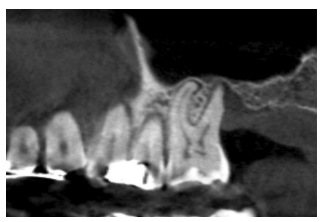

En las Figuras 2- 19 se muestra uno de los casos incluidos en el estudio.

en altura de 3,4 mm, siendo más uniforme en esta ocasión en toda la zona de la cresta. Se planifica un implante de 4,5 mm de longitud y

4,75 mm de diámetro.